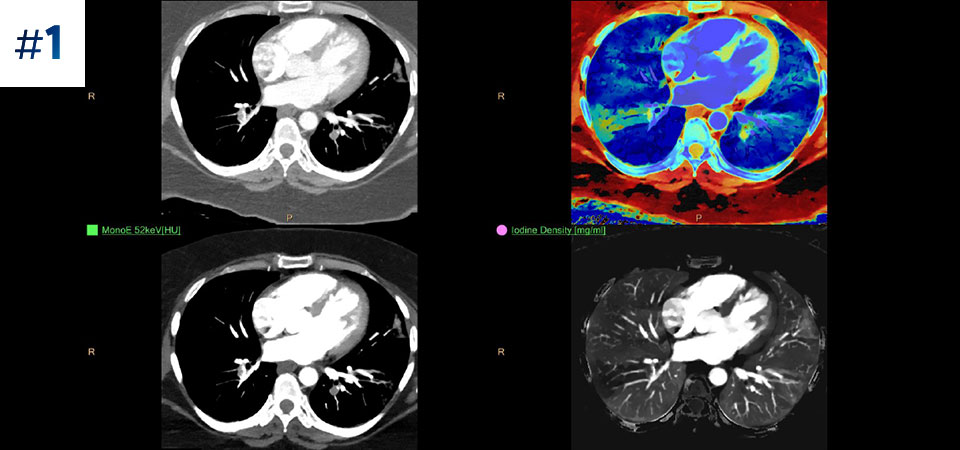

Neck mass